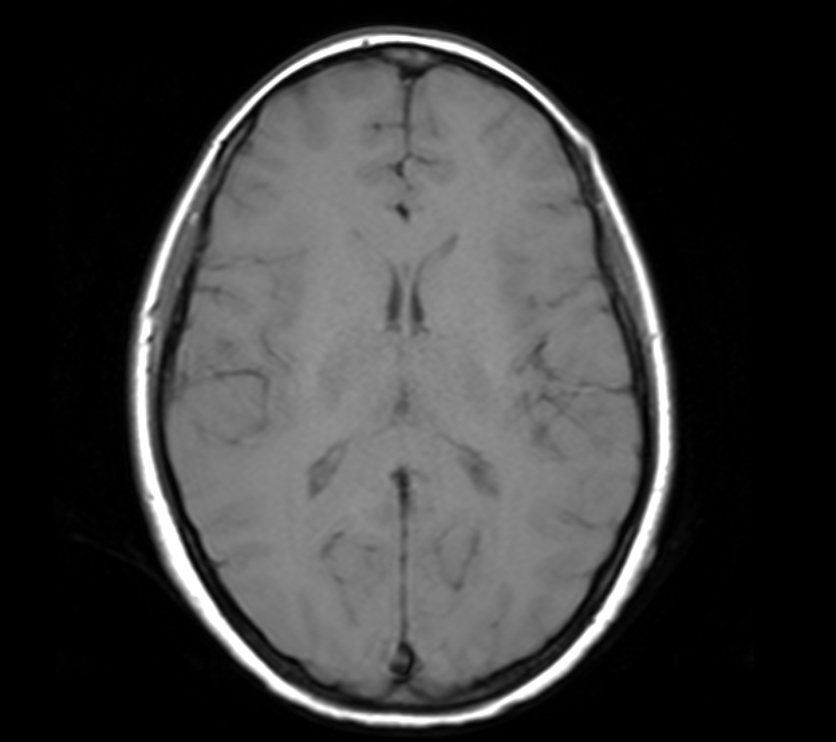

I have an MRI scan of my brain because some doctors wanted a closer look at it. Either I am a raving lunatic, or because I have a remarkable brain. One – or both.

- axial

Anyway – 3D imaging are basically slices stacked on top of / next to each other. Instead of pixels, they are three-dimentional voxels. Not super important.

The point though, is that this is done in three axes: axial, saggital, coronal. So you can generate a 3D model that have three axes to average from, instead of one – meaning that the 3D model will not look like it was built from lego. As it would, if it only was one axis. I swear, i will 3D-print my brain when I get my head around the software.